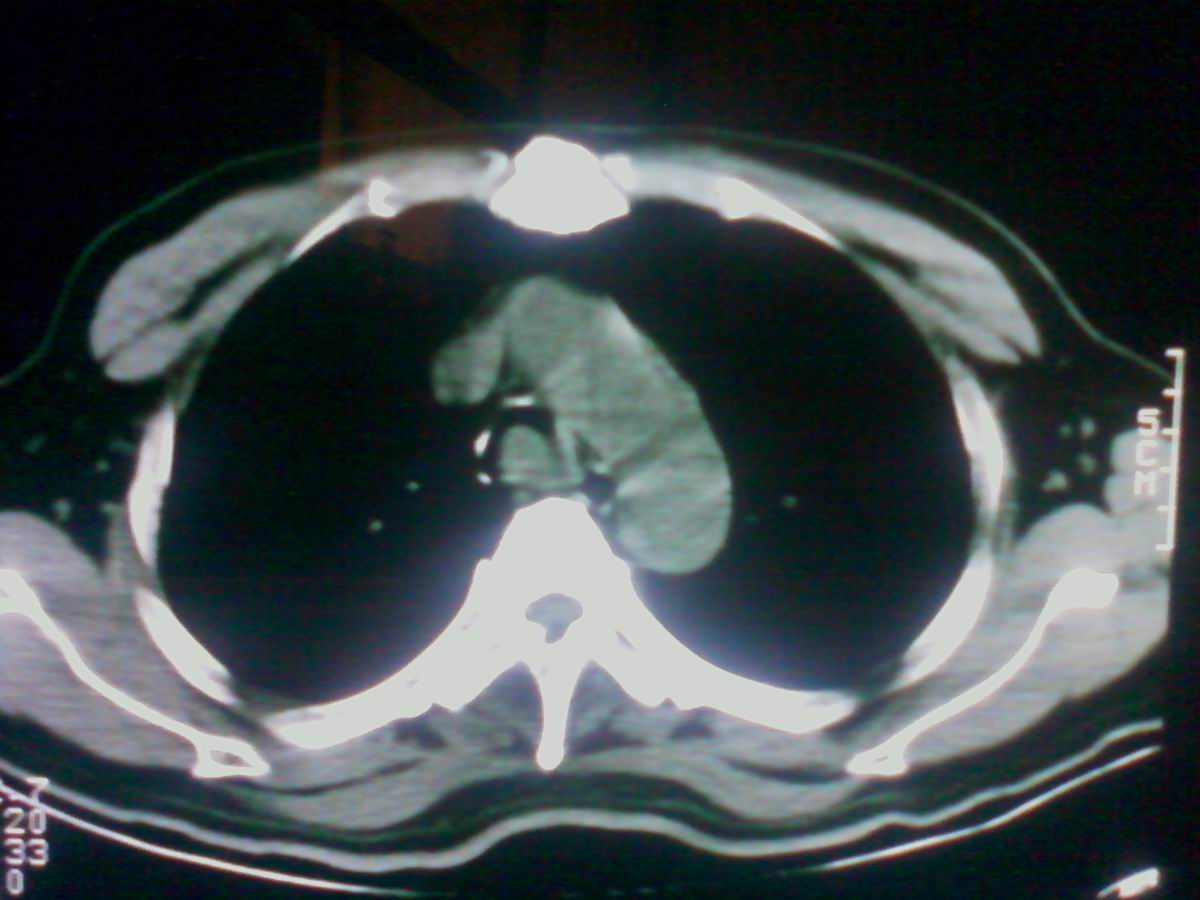

标题: CT25801:患者男性,65岁,临床提示双肺可闻及广泛罗音,看 [打印本页]

标题: CT25801:患者男性,65岁,临床提示双肺可闻及广泛罗音,看

气管后部见半圆形软组织密度病灶,考虑占位,建议气管镜除外鳞癌。

气管上段的肿瘤多为良性乳头状瘤,气管下段的肿瘤多为鳞癌,气管中段的良恶性各占一半。本例位于气管下段,先按恶性处理。不过纤支镜是免不了的。